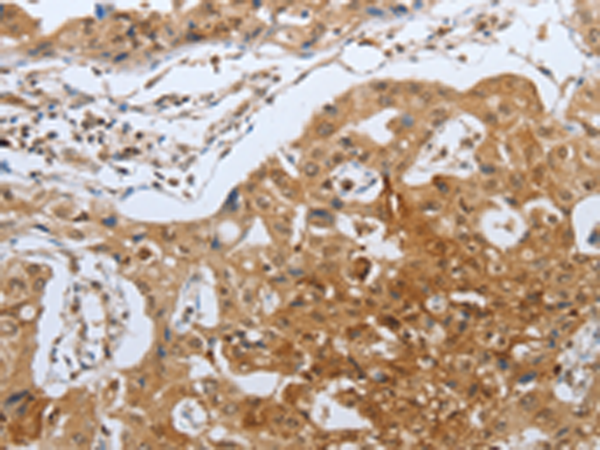

分类: 科研抗体货号: P10745别名: CEA cell adhesion molecule 5,CEA, CD66e应用: IHC反应种属: Human